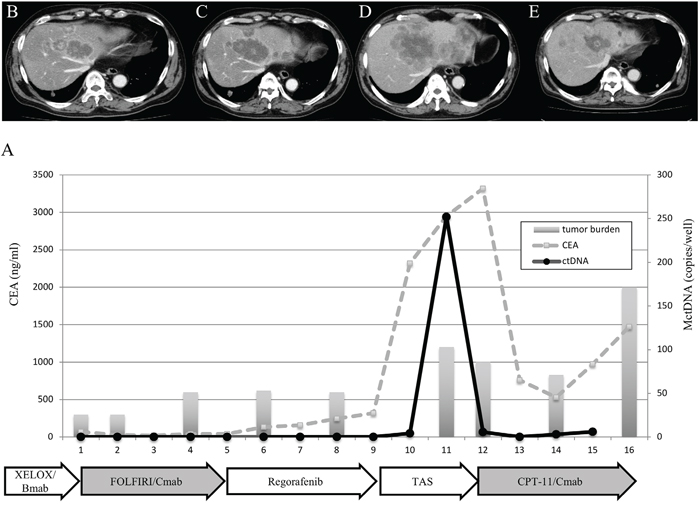

A spike in elevation was seen in six patients treated with anti-VEGF antibody or TAS-102. Although detection of MctDNA was generally seen in patients with disease progression, a spike in elevation of MctDNA was observed in patients who likely responded to drug treatments, followed by a quick disappearance. A patient who showed a drug response with a spike in elevation is shown in Figure 5. Despite there being no change in tumor size, tumors did show changes in morphology induced by TAS-102 + bevacizumab as the second-line treatment. It is reported that patients with a change in morphology show as good a drug response as those patients with a change in size, similar to a partial response and a complete response, estimated using Response Evaluation Criteria in Solid Tumours (RECIST) in not only colorectal cancer but other types of tumors such as gastrointestinal stromal tumors [23, 24, 25]. Interestingly, this patient also showed a change in tumor morphology with first-line treatment using XELOX + bevacizumab. There were some patients with a decline in MctDNA, suggesting recovery of drug sensitivity, who were then treated with re-introduction of anti-EGFR antibody. Figure 6 shows a representative image of a patient who responded to re-introduction of anti-EGFR antibody. The patient achieved a partial response and 7 months PFS with the sixth-line treatment.

Figure 6: Clinical course of a mCRC patient with multiple liver metastases (A) treated with reintroduction of CPT + cetuximab because of the disappearance of MctDNA. A 65-year-old male with multiple liver metastases is denoted as patient 85. He was treated with XELOX + bevacizumab as the first-line treatment, FOLFIRI + cetuximab as the second-line treatment, regorafenib as the third-line treatment, and TAS-102 as the fourth-line treatment.

KRAS monitoring identified continuous, intermittent, and transient changes in MctDNA. Continuous detection of MctDNA was frequently seen in MT patients, whereas intermittent detection was more often seen in WT patients. These changes may be associated with the different levels of MctDNA observed between WT and MT patients. In WT patients treated with anti-EGFR antibody, initial detection of MctDNA was likely prior to radiological disease progression (Figure 1D) [10, 9, 19]. Although detection of MctDNA was generally seen in patients with disease progression, transient changes with a spike in elevation were seen in patients in association with the drug response (Figures 3H and 5). One patient showed a transient change with a spike in elevation during treatment with TAS-102, followed by disease progression (Figure 6). MctDNA then disappeared in this patient and anti-EGFR antibody was reintroduced, which achieved a partial response and a long PFS of 7 months with the fifth-line treatment. The results suggest that the later treatment lines had a significant effect on improving the outcome for this patient. The rapid disappearance may have been induced by a delayed drug response to TAS-102 [34]. TAS-102 has a unique mechanism and works by being integrated into the DNA of the tumor cells. Such a process requires some time before an effect on the tumor is observed [35, 36]. The spike in elevation followed by disease progression may indicate a delayed drug response of TAS-102 and contributing effects associated with anti-EGFR antibody.